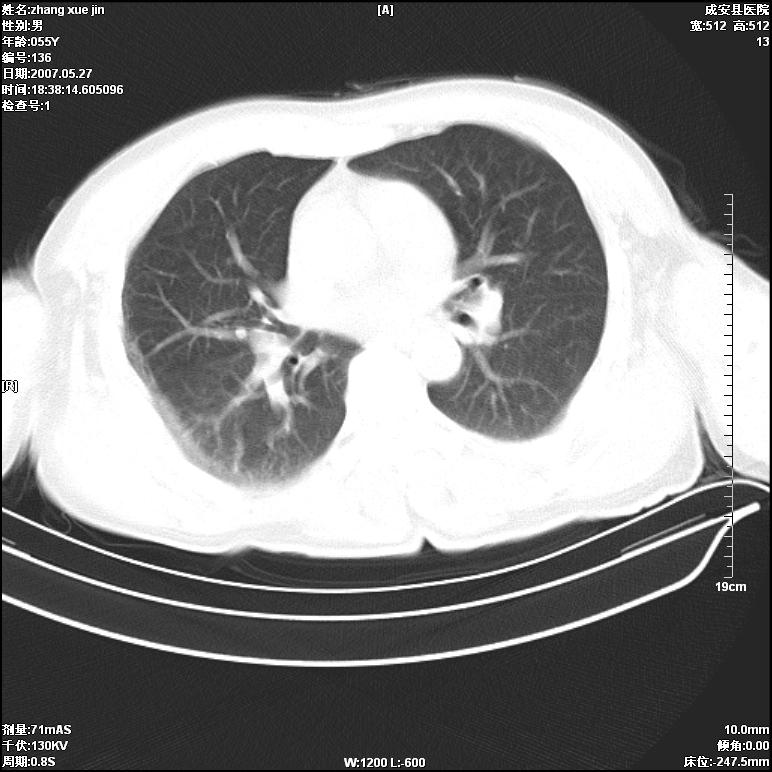

病人 男 53岁 从高处摔伤 行胸部ct检查,纵隔窗没事未上传,肺窗示,右侧胸膜下见条状稍高密度影,是胸膜下线还是右下肺轻度挫伤?意见不一,请分析。

右肺下叶胸膜下弧形窄带状模糊影,结合病史,考虑肺挫伤。

建议一周后复查,肺挫伤一般3~10天完全吸收。

左肺亦有,建议深吸气后扫描,你们是技术员扫描吧。

体位不正,左侧纵隔旁胸膜下亦见条带状略高密度影,考虑为坠积效应所致。